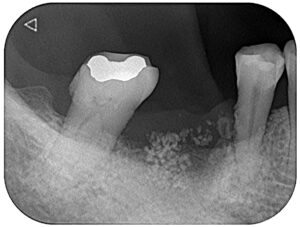

画像は右下6番(右下第一大臼歯)を失った方のレントゲン写真です。

一本でも歯を失うと、その歯の仕事を他の歯が肩代わりするため他の歯に負担がかかってしまいます。